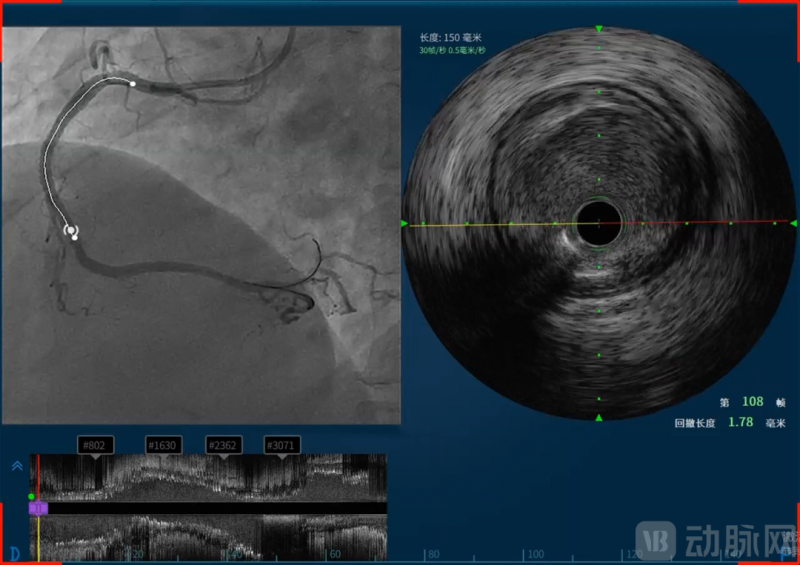

恒宇医疗的吸引力不仅在于所深耕的血管介入赛道,更在于其致力于构建的完整技术体系和难以复制的研发能力。恒宇医疗深耕血管内超声(IVUS)和光学相干断层成像(OCT)技术领域多年,形成了从核心元器件到整机设备,从单一产品到系统解决方案的全链条布局。恒宇医疗是国内少数同时掌握IVUS和OCT两项核心技术的企业,这种“双技术路线”并行的能力使其在血管介入精准诊疗领域占据了独特位置。同时融合OCT与近红外光谱(Near-Infrared Spectroscopy, NIRS)的单光源双模态OCT-NIRS技术的成功,更使恒宇医疗成功建立了OCT/IVUS/NIRS三模态成像模式,为临床诊疗提供了更为全面的解决方案。